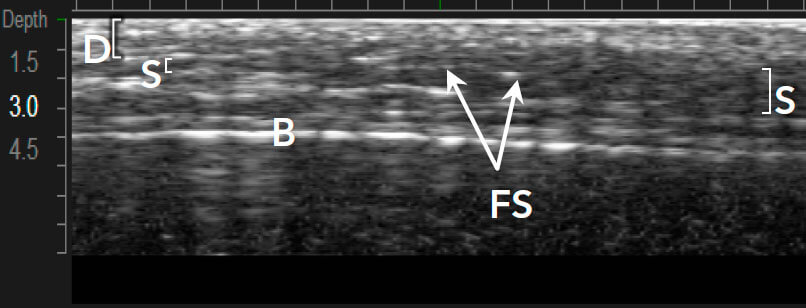

Приклади варіантів структури шкіри між індивідуальними пацієнтами 1,12

Візуалізація в реальному часі є основою Ultherapy®

Ultherapy® доставляє енергію на три глибини (1,5, 3,0 та 4,5 мм) 1,7

MFU-V дає змогу лікарям точно бачити і враховувати всі анатомічні особливості в індивідуальному плані лікування, який буде ефективним.1